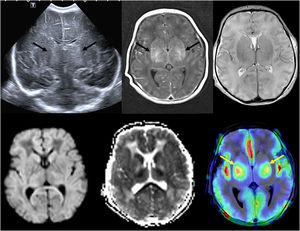

Advances in magnetic resonance imagingIn recent years, there have been significant advances in magnetic resonance imaging (MRI), especially in terms of reducing acquisition times. Rapid MRI techniques reduce acquisition times enough to avoid sedation, and is most commonly used for brain imaging, but it can also be used for assessment of acute abdomen and musculoskeletal infections. The Dixon technique achieves uniform fat suppression and also makes it possible to obtain images with and without fat suppression from a single acquisition. Diffusion tensor imaging (DTI) allows quantification of anisotropic diffusion in various directions, and subsequent construction of anisotropy maps representing the direction of tracts (tractography), which can depict microstructural changes in the brain, including physiological changes caused by myelination and brain development, the effect of various disorders, and post-treatment changes. This technique helps neurosurgeons reduce morbidity by resecting as much of the mass as possible, preserving the most important white matter tracts, such as corticospinal tract fibers, responsible for motor function, or the arcuate fasciculus, involved in language. Arterial spin labeling perfusion MRI is a perfusion method that does not require administration of gadolinium tracer but rather uses the water in blood as an endogenous tracer, thus offering the advantage of being noninvasive. It can depict perfusional changes in the brain resulting from various disorders or anomalies, such as strokes, seizures, complicated migraines, or brain neoplasms (Fig. 2). Magnetic resonance spectroscopy (MRS) provides metabolic information complementary to neuroanatomic images and is particularly useful in cerebral neoplasms, contributing to tumor grading and the assessment of treatment response. Functional MRI (fMRI) uses blood oxygenation level-dependent and its main clinical application is in presurgical planning before resection of lesions such as brain tumors, vascular malformations, or epileptogenic foci near the eloquent cortex. The eloquent areas of the brain interrogated most commonly include motor areas, language areas and visual areas, typically via various task-based fMRI paradigms. Susceptibility weighted imaging is a 3D high-spatial-resolution gradient-echo MRI sequence sensitive to the magnetic properties of blood products, calcifications and iron that can be used for detection of microhemorrhages and differentiate them from calcifications or to visualize anomalous vascularization in high-grade tumors.3

(A) Transfontanellar ultrasound performed on the first day of life in a full-term newborn with severe hypoxia-ischemia showing bilateral central gray matter injury (arrows). (B) Head MRI performed 4 days post birth showing bilateral central gray matter injury in T1- and T2-weighted images, with restricted diffusion and evidence of increased perfusion in arterial spin labeling (arrows), which has been associated with a poor prognosis.